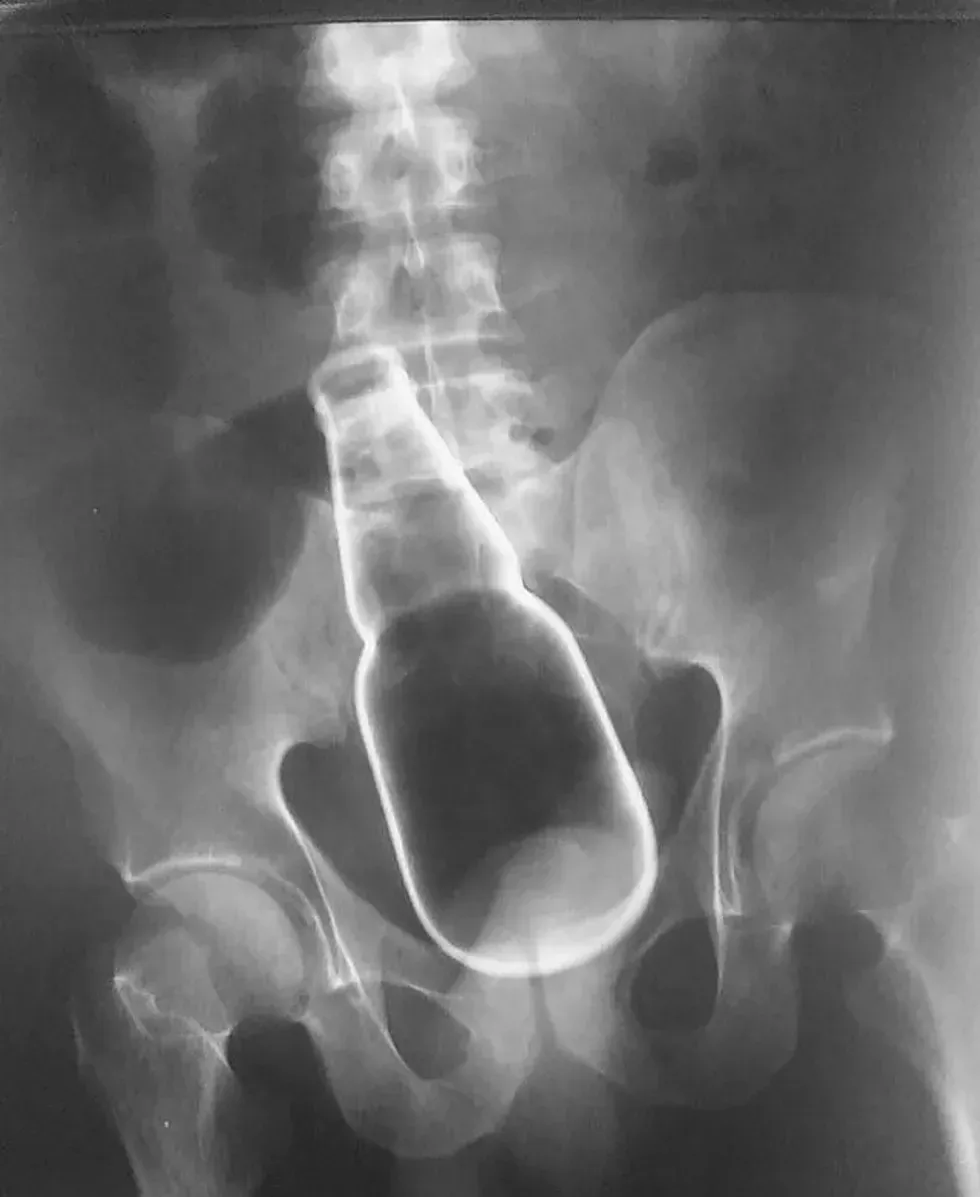

10. A dildo AND tongs